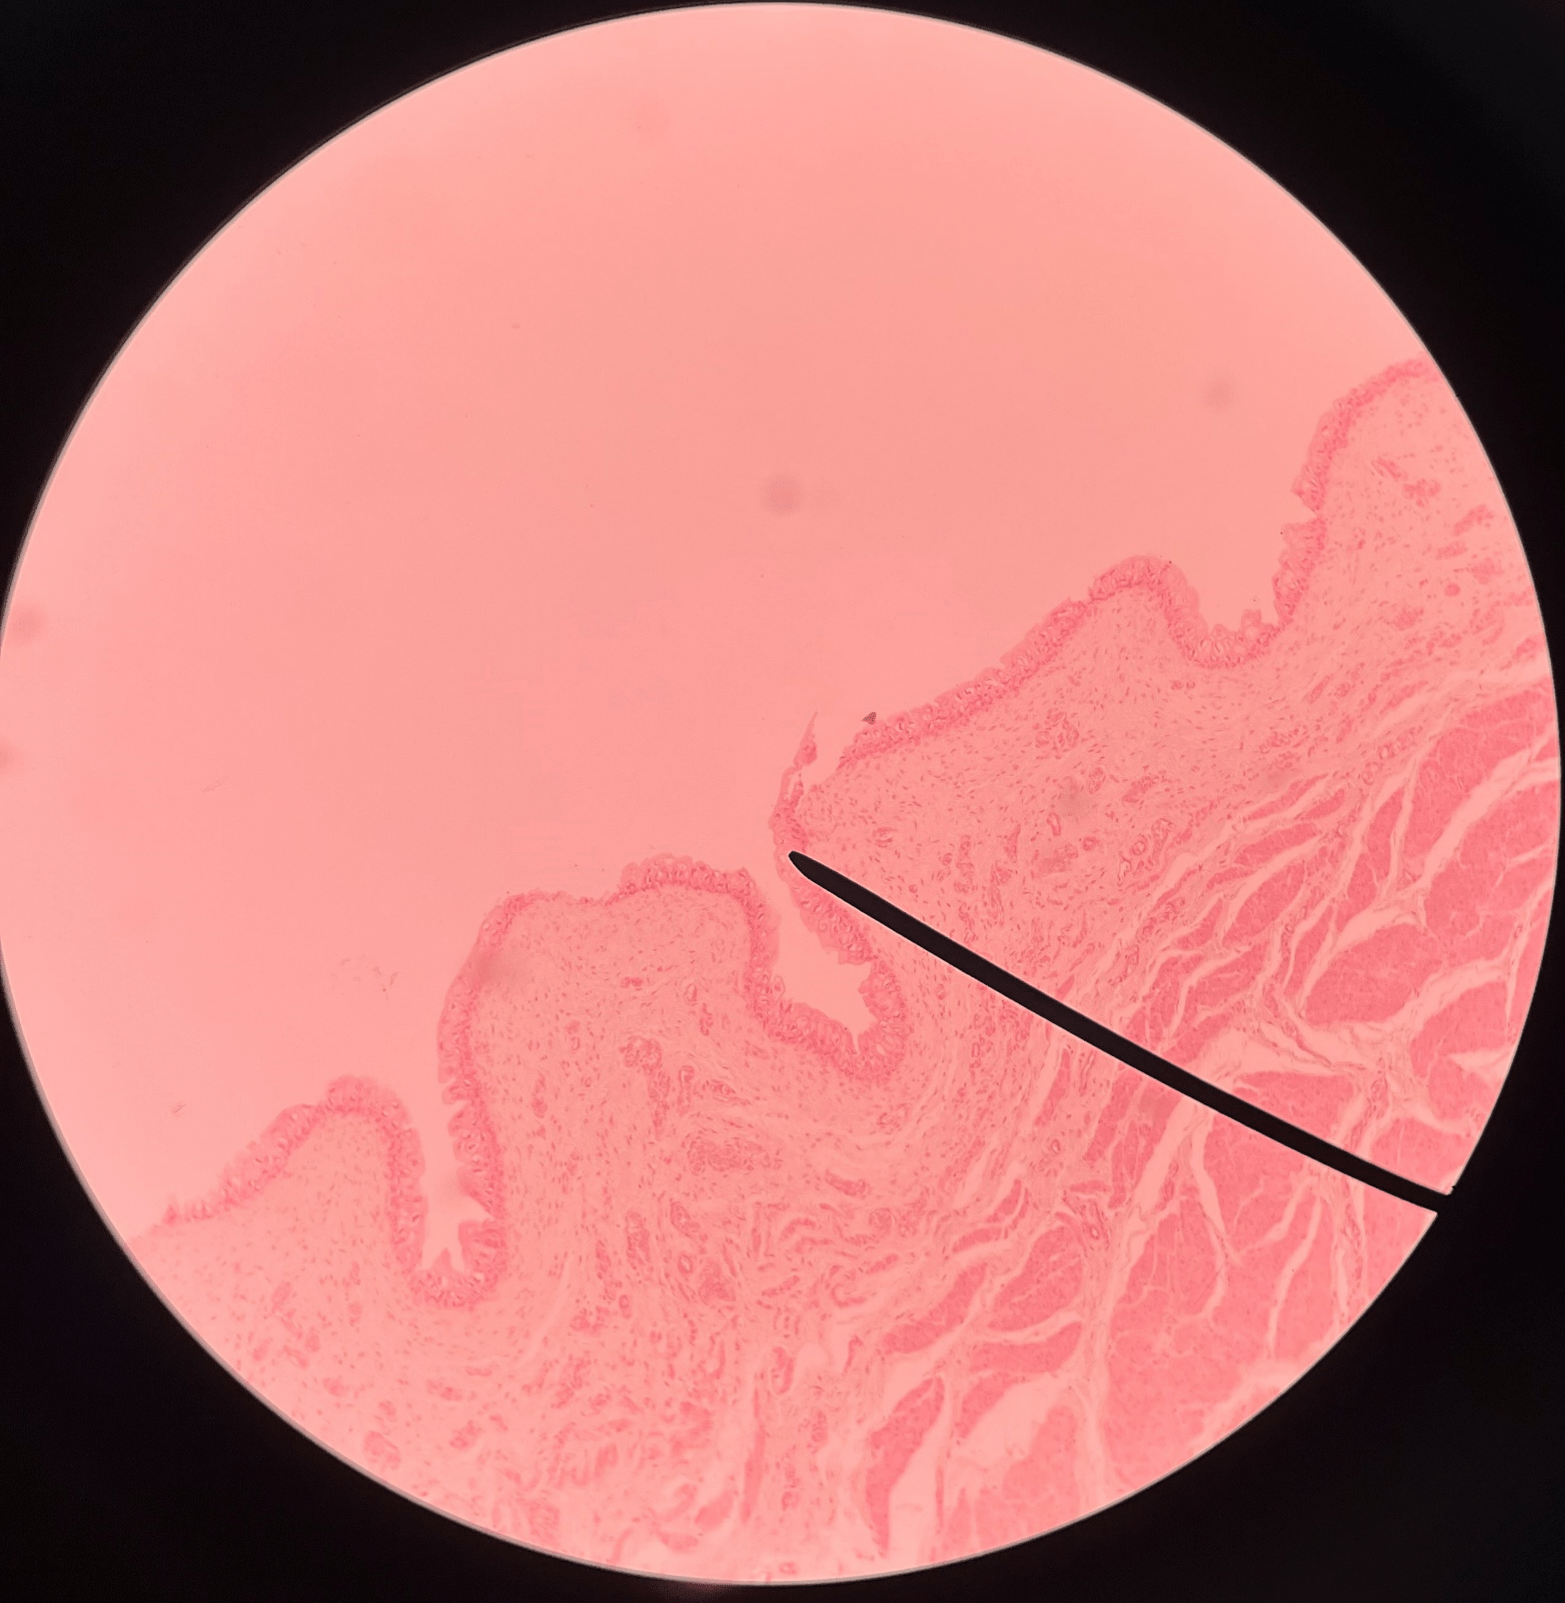

• Slide histology of the ureter.

• The outermost layer of the ureter.

• Composed of connective tissue.

• Superficial to the circular layer of the muscularis.

23

New cards

circular layer of muscularis

• Slide histology of the ureter.

• A smooth muscle layer of the ureter.

• Superficial to the longitudinal layer of the muscularis and deep to the adventitia.

New cards

longitudinal layer of muscularis

• Slide histology of the ureter.

• A smooth muscle layer of the ureter.

• Superficial to the mucosa and deep to the circular layer of the muscularis.

New cards

mucosa

• Slide histology of the ureter.

• The innermost layer of the ureter.

• Composed of urothelium.

• Faces the lumen of the ureter and is deep to the longitudinal layer of the muscularis.